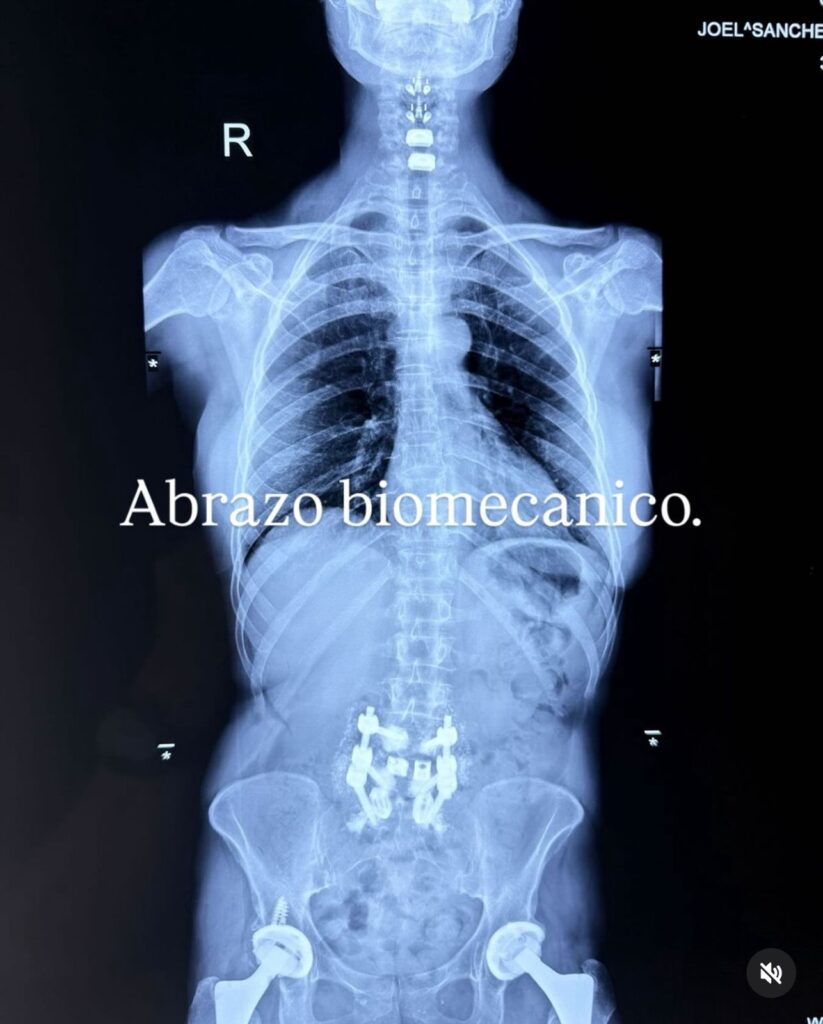

Ahora, nuevamente, La Guzmán sorprendió a sus seguidores al compartir impactantes imágenes de su columna con prótesis de titanio, tras una cirugía de emergencia que buscó aliviar el dolor y estabilizar su columna.

Alejandra compartió una radiografía que evidencia su proceso de recuperación. Con su característico humor, escribió: “Abrazo biomecánico”, mostrando cómo enfrenta los desafíos con valentía.